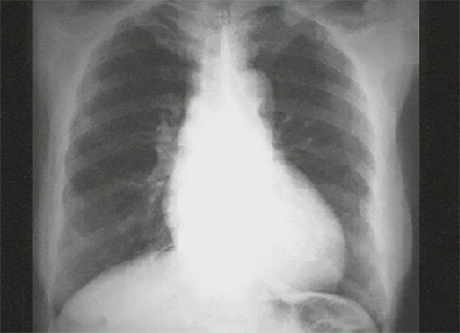

This chest X ray show left ventricular enlargement and a dilated aorta. This PA view demonstrates cardiomegaly, as evidenced by a cardiothoracic ratio greater than fifty percent. Note also the increased inferolateral cardiac border that is consistent with left ventricular enlargement due to volume overload. The ascending, transverse and descending aortic shadows are also prominent.